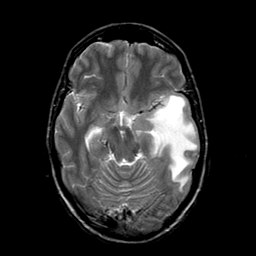

Metastatic bronchogenic carcinoma, overlay -- Slice #8

[Home][Help][Clinical] Slice 8